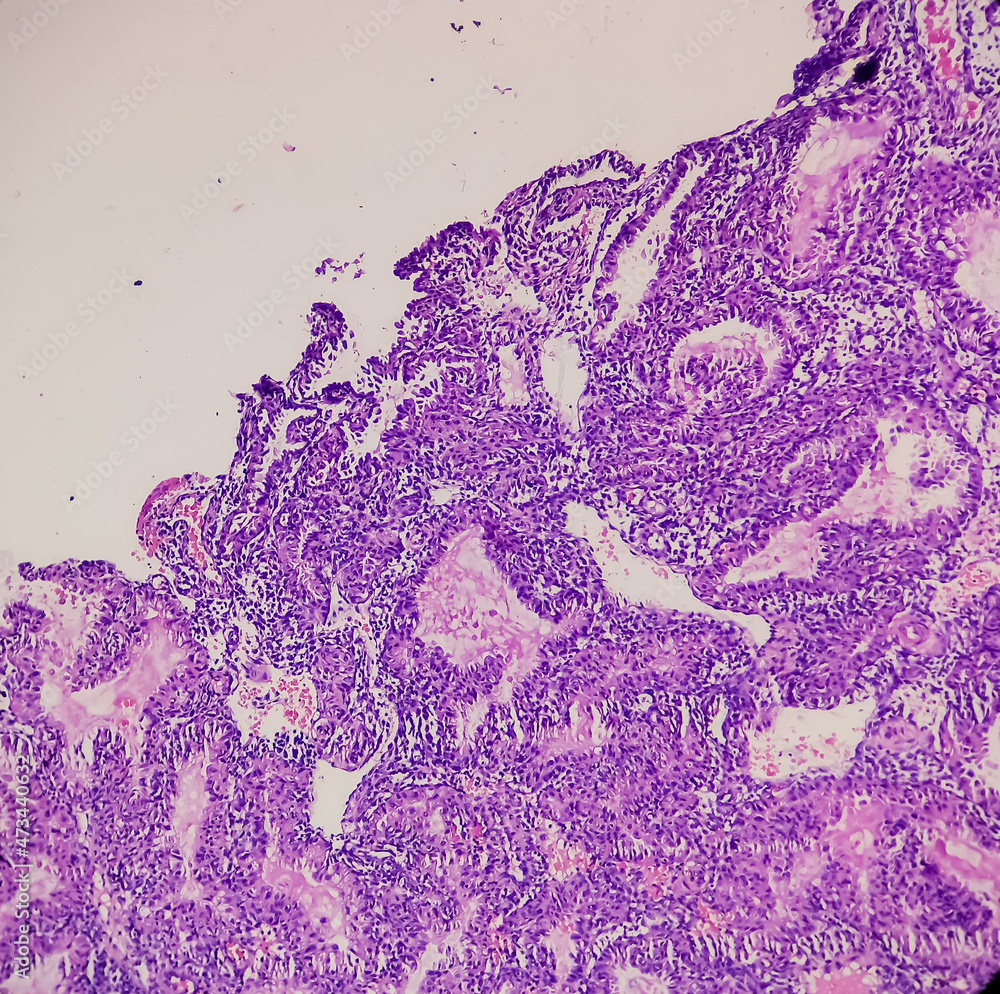

Molar Pregnancy(curettage), Microscopic Image Compatible With

Molar pregnancy(curettage), microscopic image compatible with stock.adobe.com